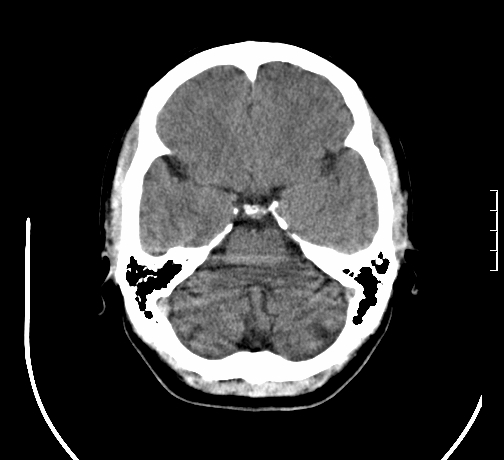

女,28岁,幼时有癫痫,常有发作,服药后可几月不发作,走路不稳3-4月,加重一月。

小脑发育畸形?

小脑萎缩。

考虑小脑发育不良,建议mri检查。

患者出现走路不稳是近几个月的事,而癫痫则有幼时就有,常发,则会常服药,癫痫药可引起小脑综合症,小脑萎缩,而小脑发育不良的主要症状不是癫痫

考虑癫痫,长期间断发服抗癫药,导致小脑综合症,小脑萎缩

考虑小脑发育不良伴小脑萎缩,建议mri检查。

小脑萎缩,原因待查,建议mri检查。

考虑小脑发育不良伴小脑萎缩,建议mri检查

考虑药物性小脑萎缩